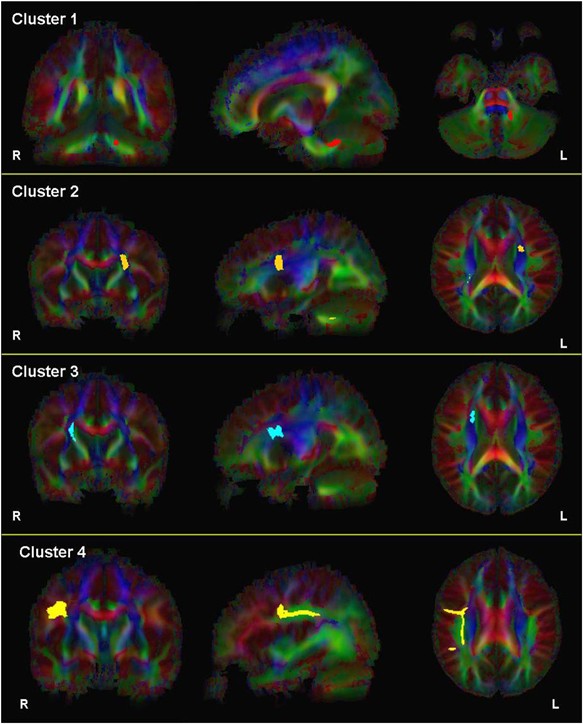

White matter regions where fractional anisotropy (FA) was significantly (p<0.001; 50 voxels) different in patients compared to healthy volunteers. A description of these regions can be found in the text and in Table 2. Note: images are in radiologic convention.

Two-dimensional images illustrating fibers passing through clusters 1–4 superimposed onto the color-coded average FA map are provided in Figure 4. Three-dimensional images illustrating fibers passing through these clusters are superimposed onto the average FA map in Figure 5. White matter passing through cluster 1 where FA was lower in patients compared to healthy volunteers appears to correspond to fibers of the pontine crossing tract. The white matter passing through clusters 2 and 3, where FA was higher in patients compared to healthy volunteers, appears to encompass fibers of the corticopontine tract (CPT), corticospinal tract (CST), and superior thalamic radiation fibers. Finally, white matter passing through cluster 4 appears to correspond to fibers of the superior longitudinal fasciculus (SLF). Visual inspection of fiber tracts indicates convergence of white matter from clusters 1–3 in the vicinity of the pontine crossing tract.

2D images illustrating fibers passing through clusters 1–4, respectively, superimposed onto the color-coded average fractional anisotropy (FA) map of all subjects. Note: images are in radiologic convention. Fibers passing through clusters 1–4 are illustrated in red, orange, blue, and yellow, respectively.

Average FA along the four sets of extracted white matter bundles was computed separately for patients and healthy volunteers. White matter FA along fibers of the pontine crossing tract (extracted from cluster 1) had significantly lower mean FA in patients compared to healthy volunteers along its length (t=−3.32, d.f.=66, p=0.001). In addition, FA along fibers of the CST and CPT and thalamic radiation fibers extracted from cluster 2 was significantly higher in patients compared to healthy volunteers (t=3.21, d.f.=66, p=0.002), but did not differ significantly between groups for fibers extracted from cluster 3 (t=1.38, d.f.=66, p=0.172). Lastly, white matter FA (extracted from cluster 4) along fibers of the SLF did not differ significantly between groups (t=2.01, d.f.=66, p=0.048) following correction for multiple comparisons.